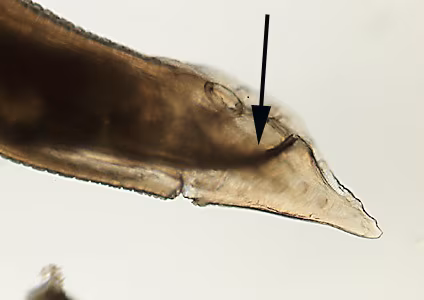

A state public health laboratory received three worms from a regional commercial laboratory for identification. The public health laboratory submitted the worms to the CDC/DPDx Team for diagnostic assistance. The submission form indicated that how and where the worms were collected was not provided by the commercial laboratory. Figure A shows all three worms for gross presentation and size determination. A dissecting microscope was used to observe morphologic features. Figures A and B shows two separate focal planes of the anterior of one worm; Figures C, D and E show three aspects of the tail. What is your diagnosis? Based on what morphologic features.

Figure D